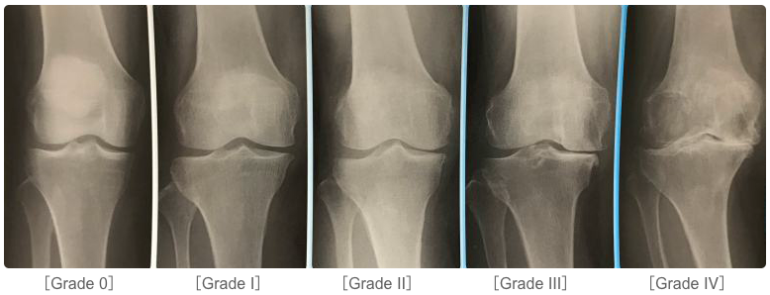

変形性膝関節症の分類では5段階で分類されています。

Grade 0:正常

Grade Ⅰ:関節裂隙狭小のないわずかの骨棘形成 , または軟骨下骨硬化

Grade Ⅱ:関節裂隙狭小(25% 以下)あるも骨変化なし

Grade Ⅲ:関節狭小(50%~75%)と骨棘形成 , 骨硬化像

Grade Ⅳ:骨変化が著しく,関節裂隙狭小(75% 以上)を伴う

あくまでも私の見解になりますが、Grade Ⅲまではある程度効果が期待できると思います。

しかし、Grade Ⅳになると関節軟骨が消失しており、変形が重度であるため効果が薄いかもしれません。

Grade Ⅳの場合は人工膝関節全置換術を受けるのがいいでしょう。ですが、人工膝関節全置換術を躊躇される場合は一度PRP注射を試してみてもよいかもしれません。